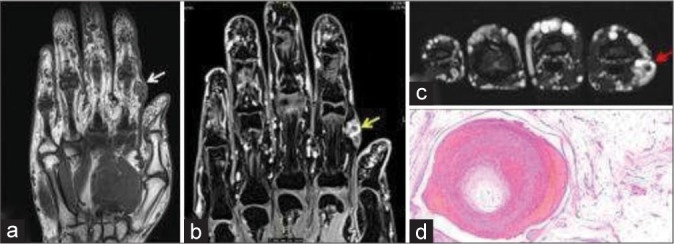

Soft tissue tumors involving the hand are common and most often benign. It is important to know the spectrum of soft tissue tumors of the hand and understand the typical as well as atypical imaging features are seen on different imaging modalities. The imaging features are largely determined by the tumor histopathology; thus, the basic idea about the tumor histopathology will always be useful. This article intends to focus on a comprehensive approach including demographics, clinical presentation, and imaging findings required to diagnose the tumor definitely or narrow the differentials. This article discusses common soft tissue tumor mimics of the hand as well, however, excludes the bone tumors for the sake of brevity.